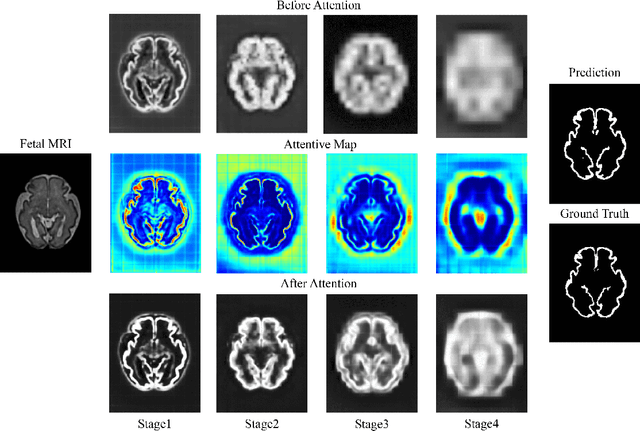

Abstract:Fetal cortical plate segmentation is essential in quantitative analysis of fetal brain maturation and cortical folding. Manual segmentation of the cortical plate, or manual refinement of automatic segmentations is tedious and time consuming, and automatic segmentation of the cortical plate is challenged by the relatively low resolution of the reconstructed fetal brain MRI scans compared to the thin structure of the cortical plate, partial voluming, and the wide range of variations in the morphology of the cortical plate as the brain matures during gestation. To reduce the burden of manual refinement of segmentations, we have developed a new and powerful deep learning segmentation method that exploits new deep attentive modules with mixed kernel convolutions within a fully convolutional neural network architecture that utilizes deep supervision and residual connections. Quantitative evaluation based on several performance measures and expert evaluations show that our method outperformed several state-of-the-art deep models for segmentation, as well as a state-of-the-art multi-atlas segmentation technique. In particular, we achieved average Dice similarity coefficient of 0.87, average Hausdroff distance of 0.96mm, and average symmetric surface difference of 0.28mm in cortical plate segmentation on reconstructed fetal brain MRI scans of fetuses scanned in the gestational age range of 16 to 39 weeks. By generating accurate cortical plate segmentations in less than 2 minutes, our method can facilitate and accelerate large-scale studies on normal and altered fetal brain cortical maturation and folding.